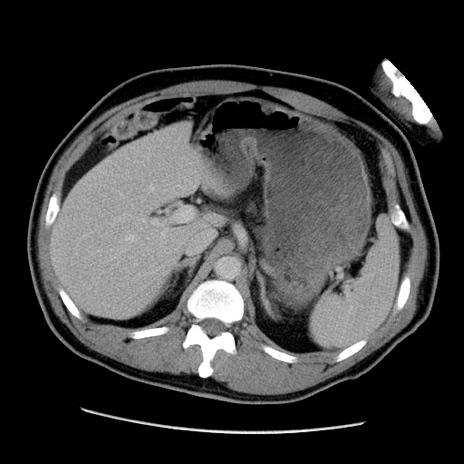

症例22(横断像)

【症例】50歳代男性

【主訴】腹痛

【現病歴】AVMからの被殻出血のため回復期リハ病棟入院中。 本日午後3時頃急に下腹部痛が出現した。

【既往歴】AVM、被殻出血、虫垂炎、高血圧

【身体所見】意識晴明、左半身不全麻痺、会話の理解は良好、36.5°C、腹部:膨隆、全体に板状硬、下腹部正中に圧痛点あり、反跳痛-、筋性防御不明、右下腹部にope scar

【データ】WBC 9400、CRP 0.06